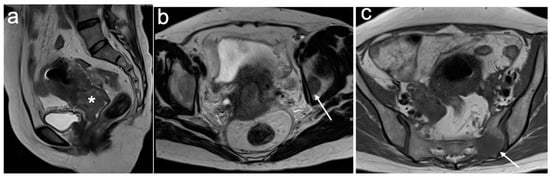

4. FIGO Stage I

5. FIGO Stage II

6. FIGO Stage III

7. FIGO Stage IV